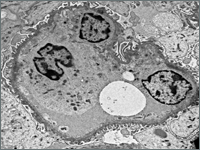

OtherOne of the most common causes of hematuria in children is acute glomerulonephritis. Diseases genetically determined, including Alport syndrome, are among the rarer causes.